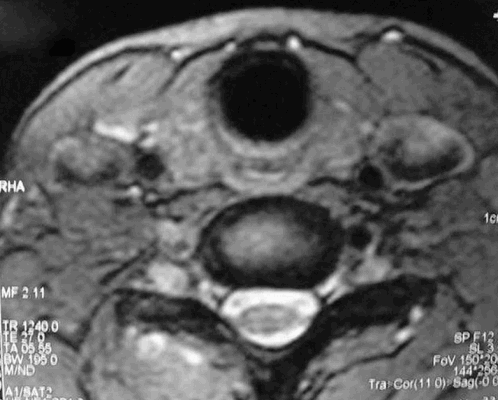

Новообразование в области щитовидной железы

Магнитно-резонансная томография щитовидной железы применяется для диагностики поражений этого органа, в том числе злокачественной природы. Исследование также применяется с профилактической целью.